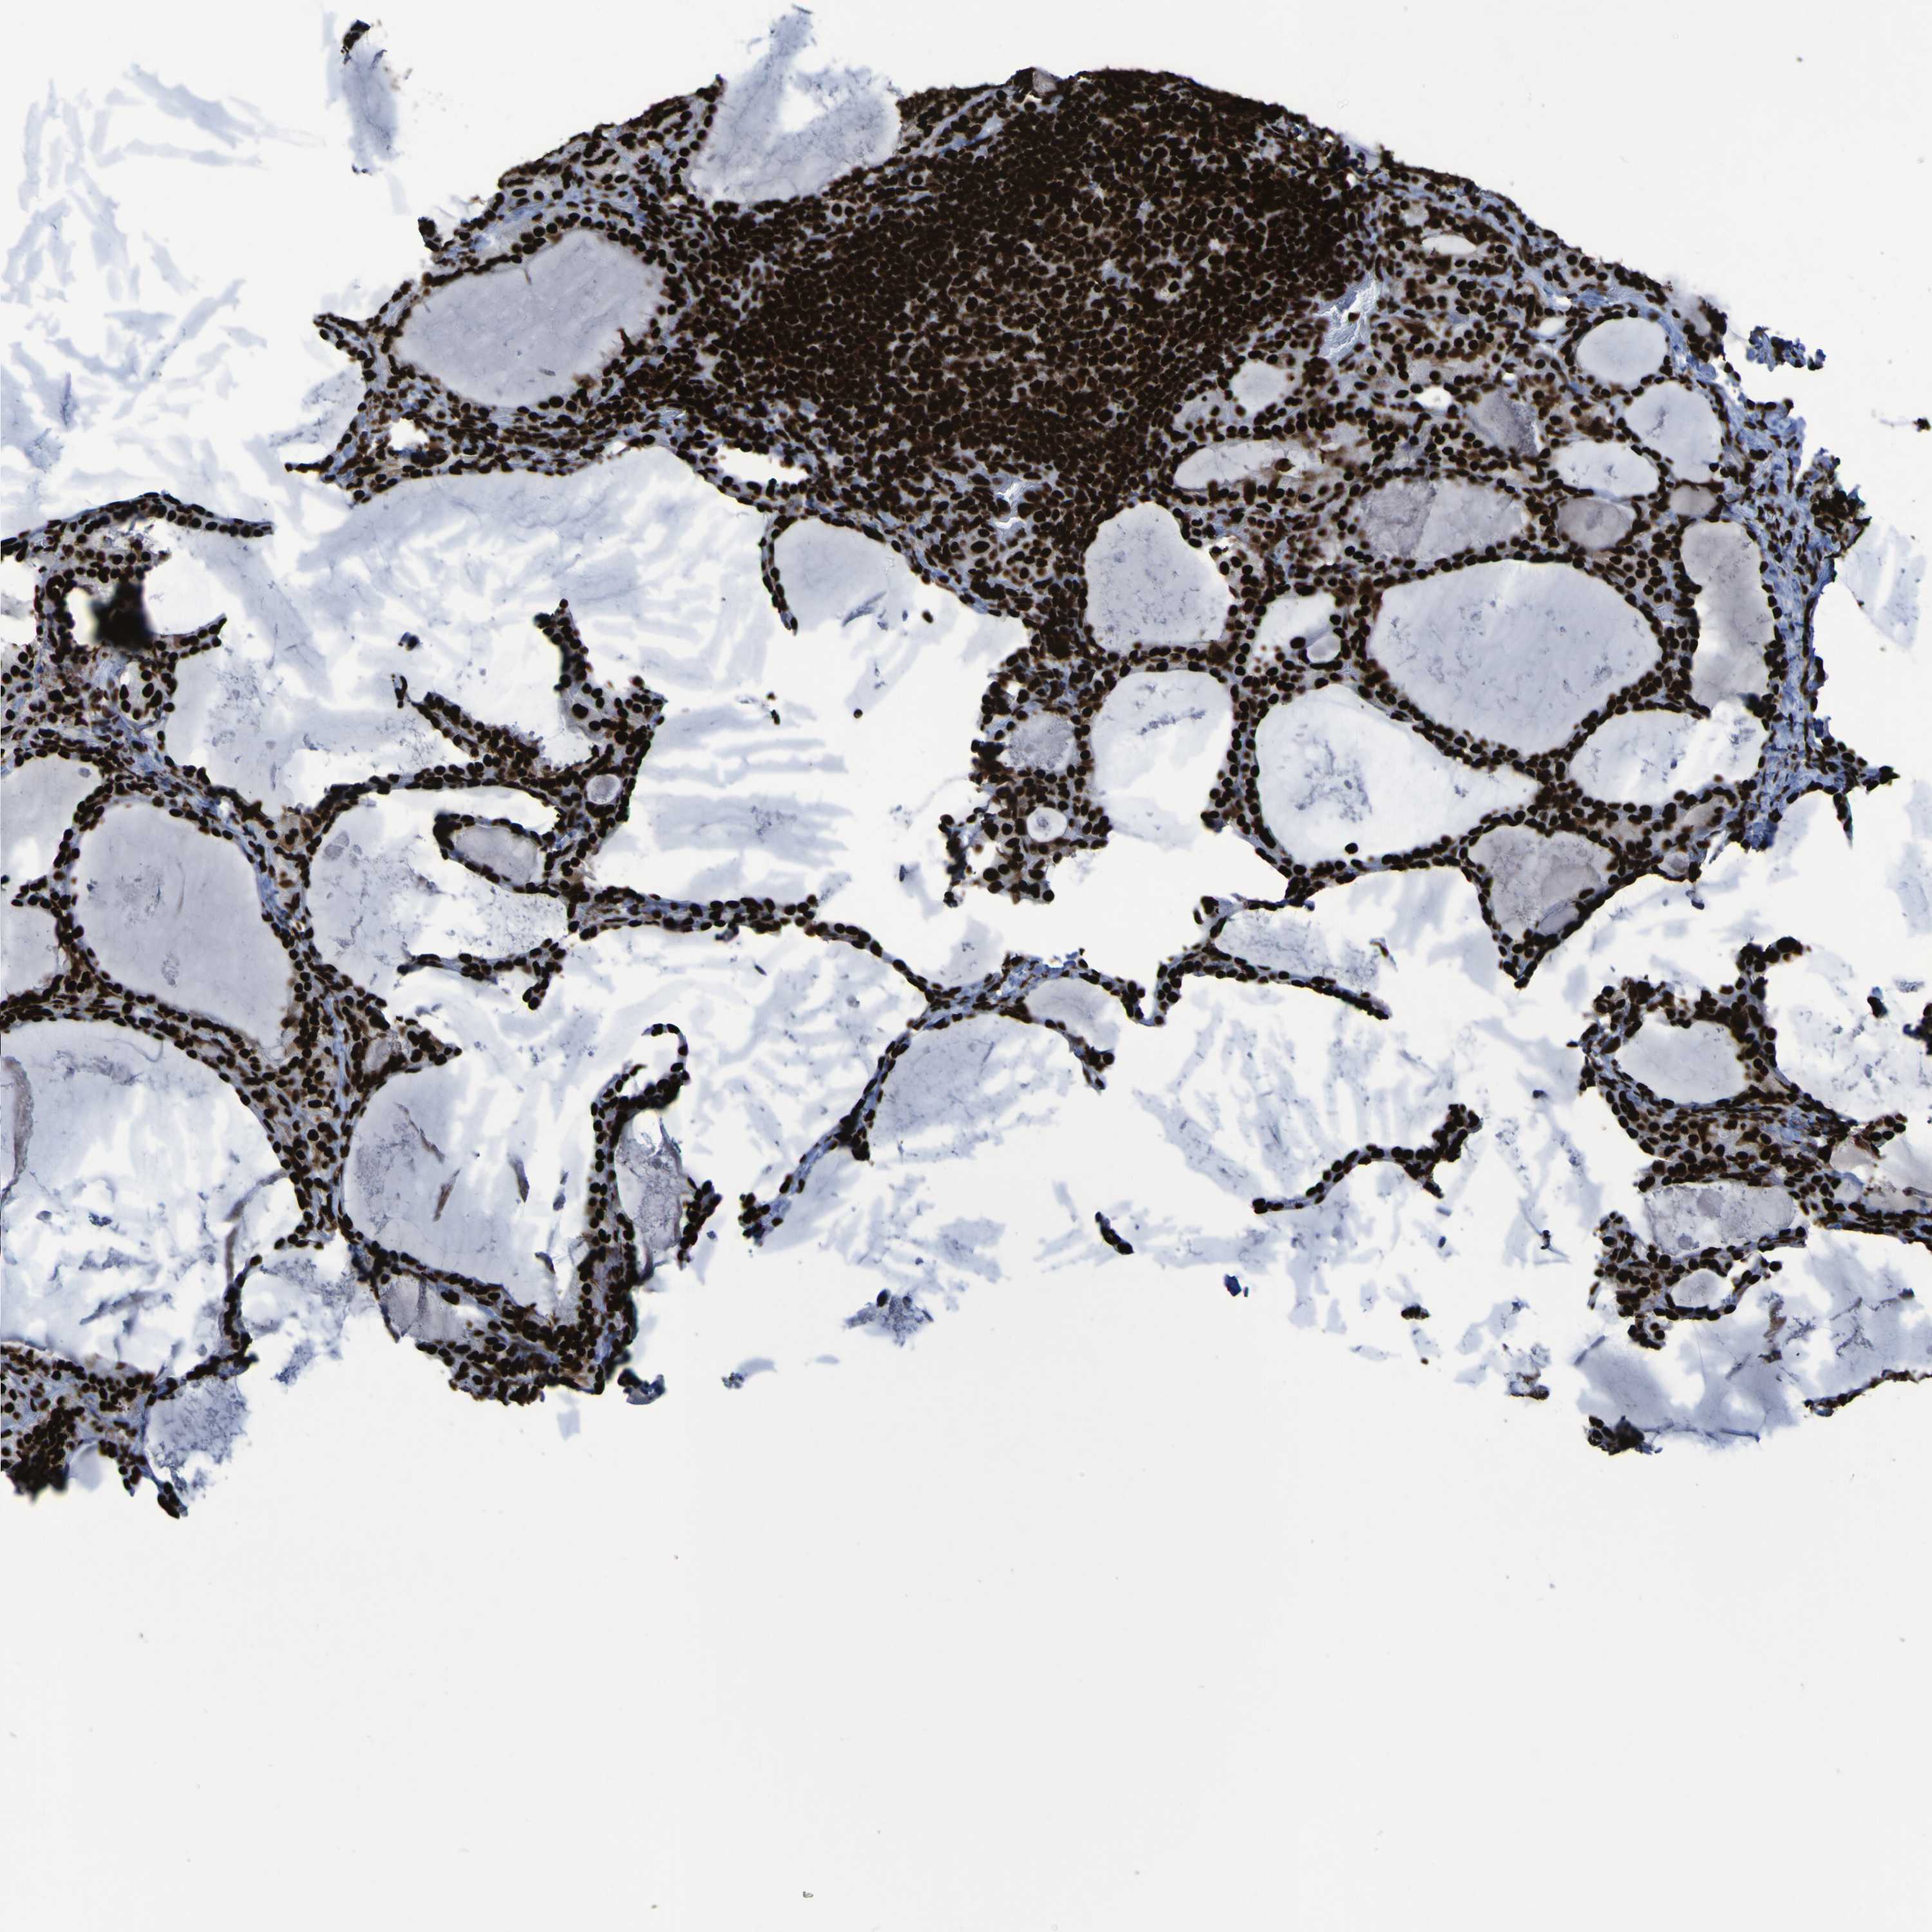

THYROID CANCER - Protein expressioni

A mouse-over function shows sample information and annotation data. Click on an image to view it in a full screen mode. Samples can be filtered based on level of antibody staining by selecting one or several of the following categories: high, medium, low and not detected. The assay and annotation is described here.

Note that samples used for immunohistochemistry by the Human Protein Atlas do not correspond to samples in the TCGA dataset.

Antibody stainingi

Antibody staining in the annotated cell types in the current human tissue is reported as not detected, low, medium, or high, based on conventional immunohistochemistry profiling in selected tissues. This score is based on the combination of the staining intensity and fraction of stained cells.

Each image is clickable and will lead to virtual microscopy that enables deeper exploration of all samples and also displays staining intensity scores, fraction scores and subcellular localization as well as patient and tissue information for each sample.

Antibody HPA011384

Antibody CAB012983

Staining

High

Medium

Low

Not detected

Intensity

Strong

Moderate

Weak

Negative

Quantity

>75%

75%-25%

<25%

None

Location

Nuclear

Cytoplasmic/membranous

Cytoplasmic/membranous,nuclear

Papillary adenocarcinoma, NOS

Follicular adenoma carcinoma, NOS